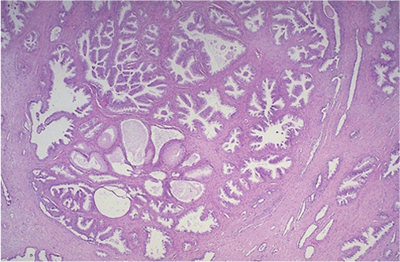

What type of necrosis is demonstrated in these images?

Answer

• Gangrenous

• Coagulative

• Fat

• Caseous